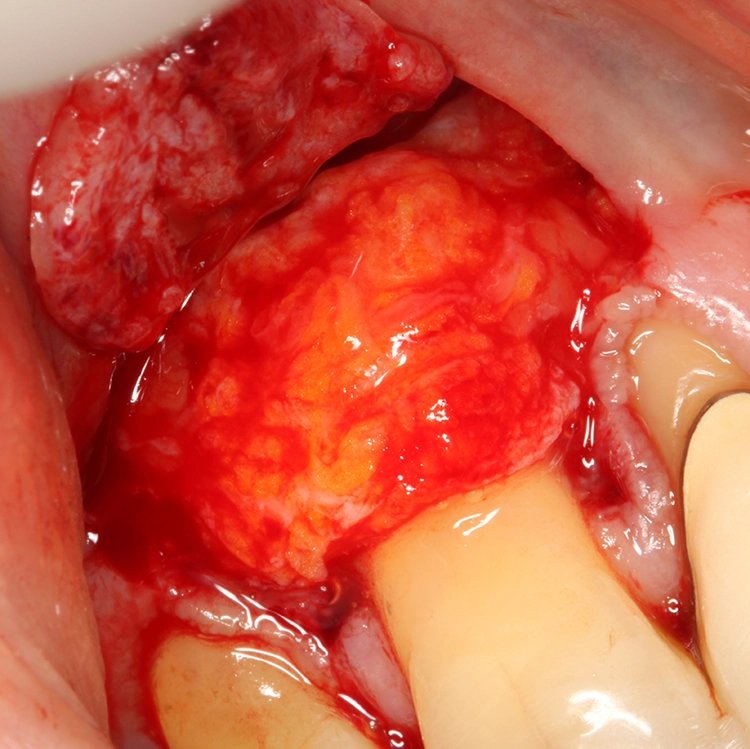

Für die plastische Rezessionsdeckung an den Zähnen 13 und 23 mithilfe von doppelten Papillalappen nach Cohnen und Ross [2], Bindegewebetransplantaten und Schmelz-Matrix-Proteinderivat wurde die Schnittführung mit Split-Flap-Bildung so gewählt, dass möglichst viel keratinisierte Gingiva generiert werden konnte und der Mindestabstand zu den Nachbarparodontien von 1 mm eingehalten wurde (Abb. 13). Ein Gewebekeil wurde apikal der Rezession entfernt und vorerst nur ein Läppchen gesplittet (Abb. 14). Die beiden gesplitteten Läppchen wurden vernäht, wobei ein Mukosaläppchen noch unmobilisiert blieb, um das Aneinandernähen zu erleichtern. Das Vernähen erfolgte von koronal nach apikal, danach wurde das zweite Läppchen vollständig mobilisiert (Abb. 15).

Egger/Wermuth/GrevenAus dem Gaumen wurde mit der Single-Inzisionstechnik [5] ein Bindegewebetransplantat entnommen (Abb. 16). Die Konditionierung der Wurzeloberfläche erfolgte mit EDTA 24%. Schließlich wurde Schmelz-Matrix-Protein (Prefgel/Emdogain, Straumann, Schweiz) appliziert und das Bindegewebetransplantat in der gewünschten Position fixiert. Der Wundverschluss wurde mit nicht resorbierbarem Nahtmaterial (7.0 monofilamentes Polyvinylidenfluorid, Seralene, Serag Wiessner) durchgeführt, die Feinadaptation im Übergangsbereich der beiden lateralen Verschiebelappen mit Einzelknopfnähten. Es wurde kein Wundverschluss per primam angestrebt, um nicht zu viel lateralen Zug auf die Läppchen auszuüben.